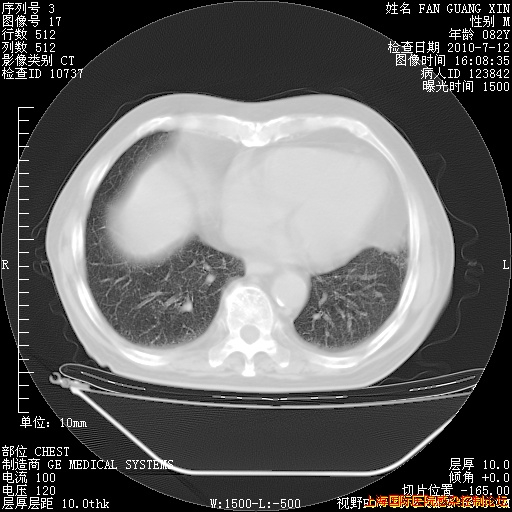

今天复查CT

今天CT

整整相隔30天的肺部CT好像有所好转啊。甲强龙减量第3天,需要观察体温。

海管,自昨日你和我通完话后,不知您岳父消化道症状有无缓解?体温怎样?阅读7.12日胸部ct,个人认为目前激素治疗是有效的,甲强龙减量是适宜的。因在抗痨治疗,需密切观察肝功、肾功能和血常规。不过,老年、长期住院和大量使用激素,很担心菌群失调发生